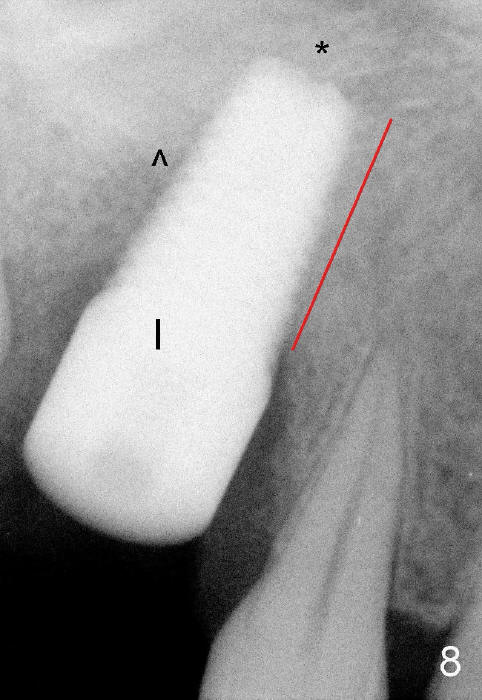

It appears that when a 7x17 mm implant is placed (Fig.8), the bone contact is increased vertically (red line) as the diameter of the implant increases.  ^: sinus floor; *: bone present apical to the implant.